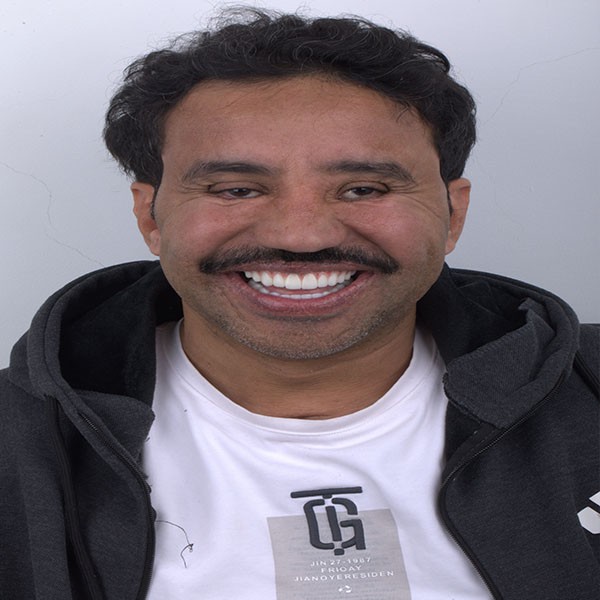

Founded in 2012, our clinic has over a decade of trusted experience in delivering world-class dental care. We specialize in full mouth rehabilitation and implantology, while also offering comprehensive services across all dental specialties including fixed and removable prosthodontics, restorative, endodontics, periodontics, maxillofacial surgery, orthodontics, and pediatric dentistry. Our strength lies in our dedicated team of highly skilled dentists, each bringing diverse expertise, working together with a shared passion for teamwork to ensure every patient receives a personalized care. Equipped with a state-of-the-art CAD/CAM lab, in-house CBCT, and panoramic X-ray technology, we provide a seamless workflow and the convenience of same-day crown deliveries. Our commitment is to combine expertise, precision, and the latest innovations in modern dentistry to create healthy, confident smiles in a professional and welcoming environment.